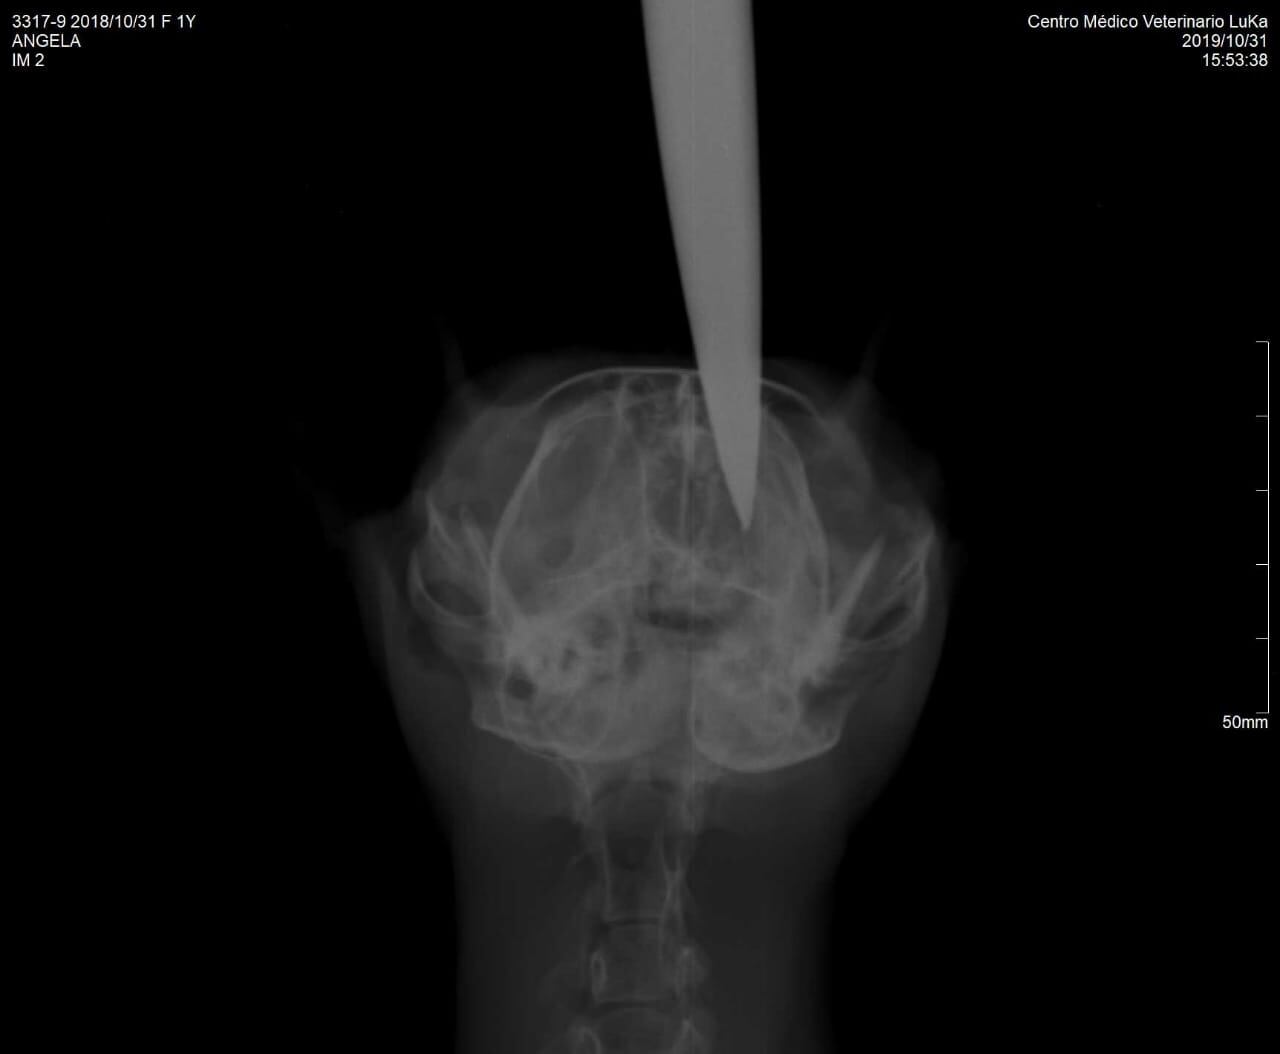

Luego la rescatista llevó a la gatica a la veterinaria Acrópolis, en Cartago y la doctora que la atendió dijo que había que hacerle unas placas, por lo que la llevó a la veterinaria Luka y ahí le hicieron los exámenes.

En las placas se logra ver que el cuchillo tocó el cerebro de la gatica, por lo que el pronóstico es reservado y le recomendaron a Maroto que la llevara donde un especialista en ortopedia.